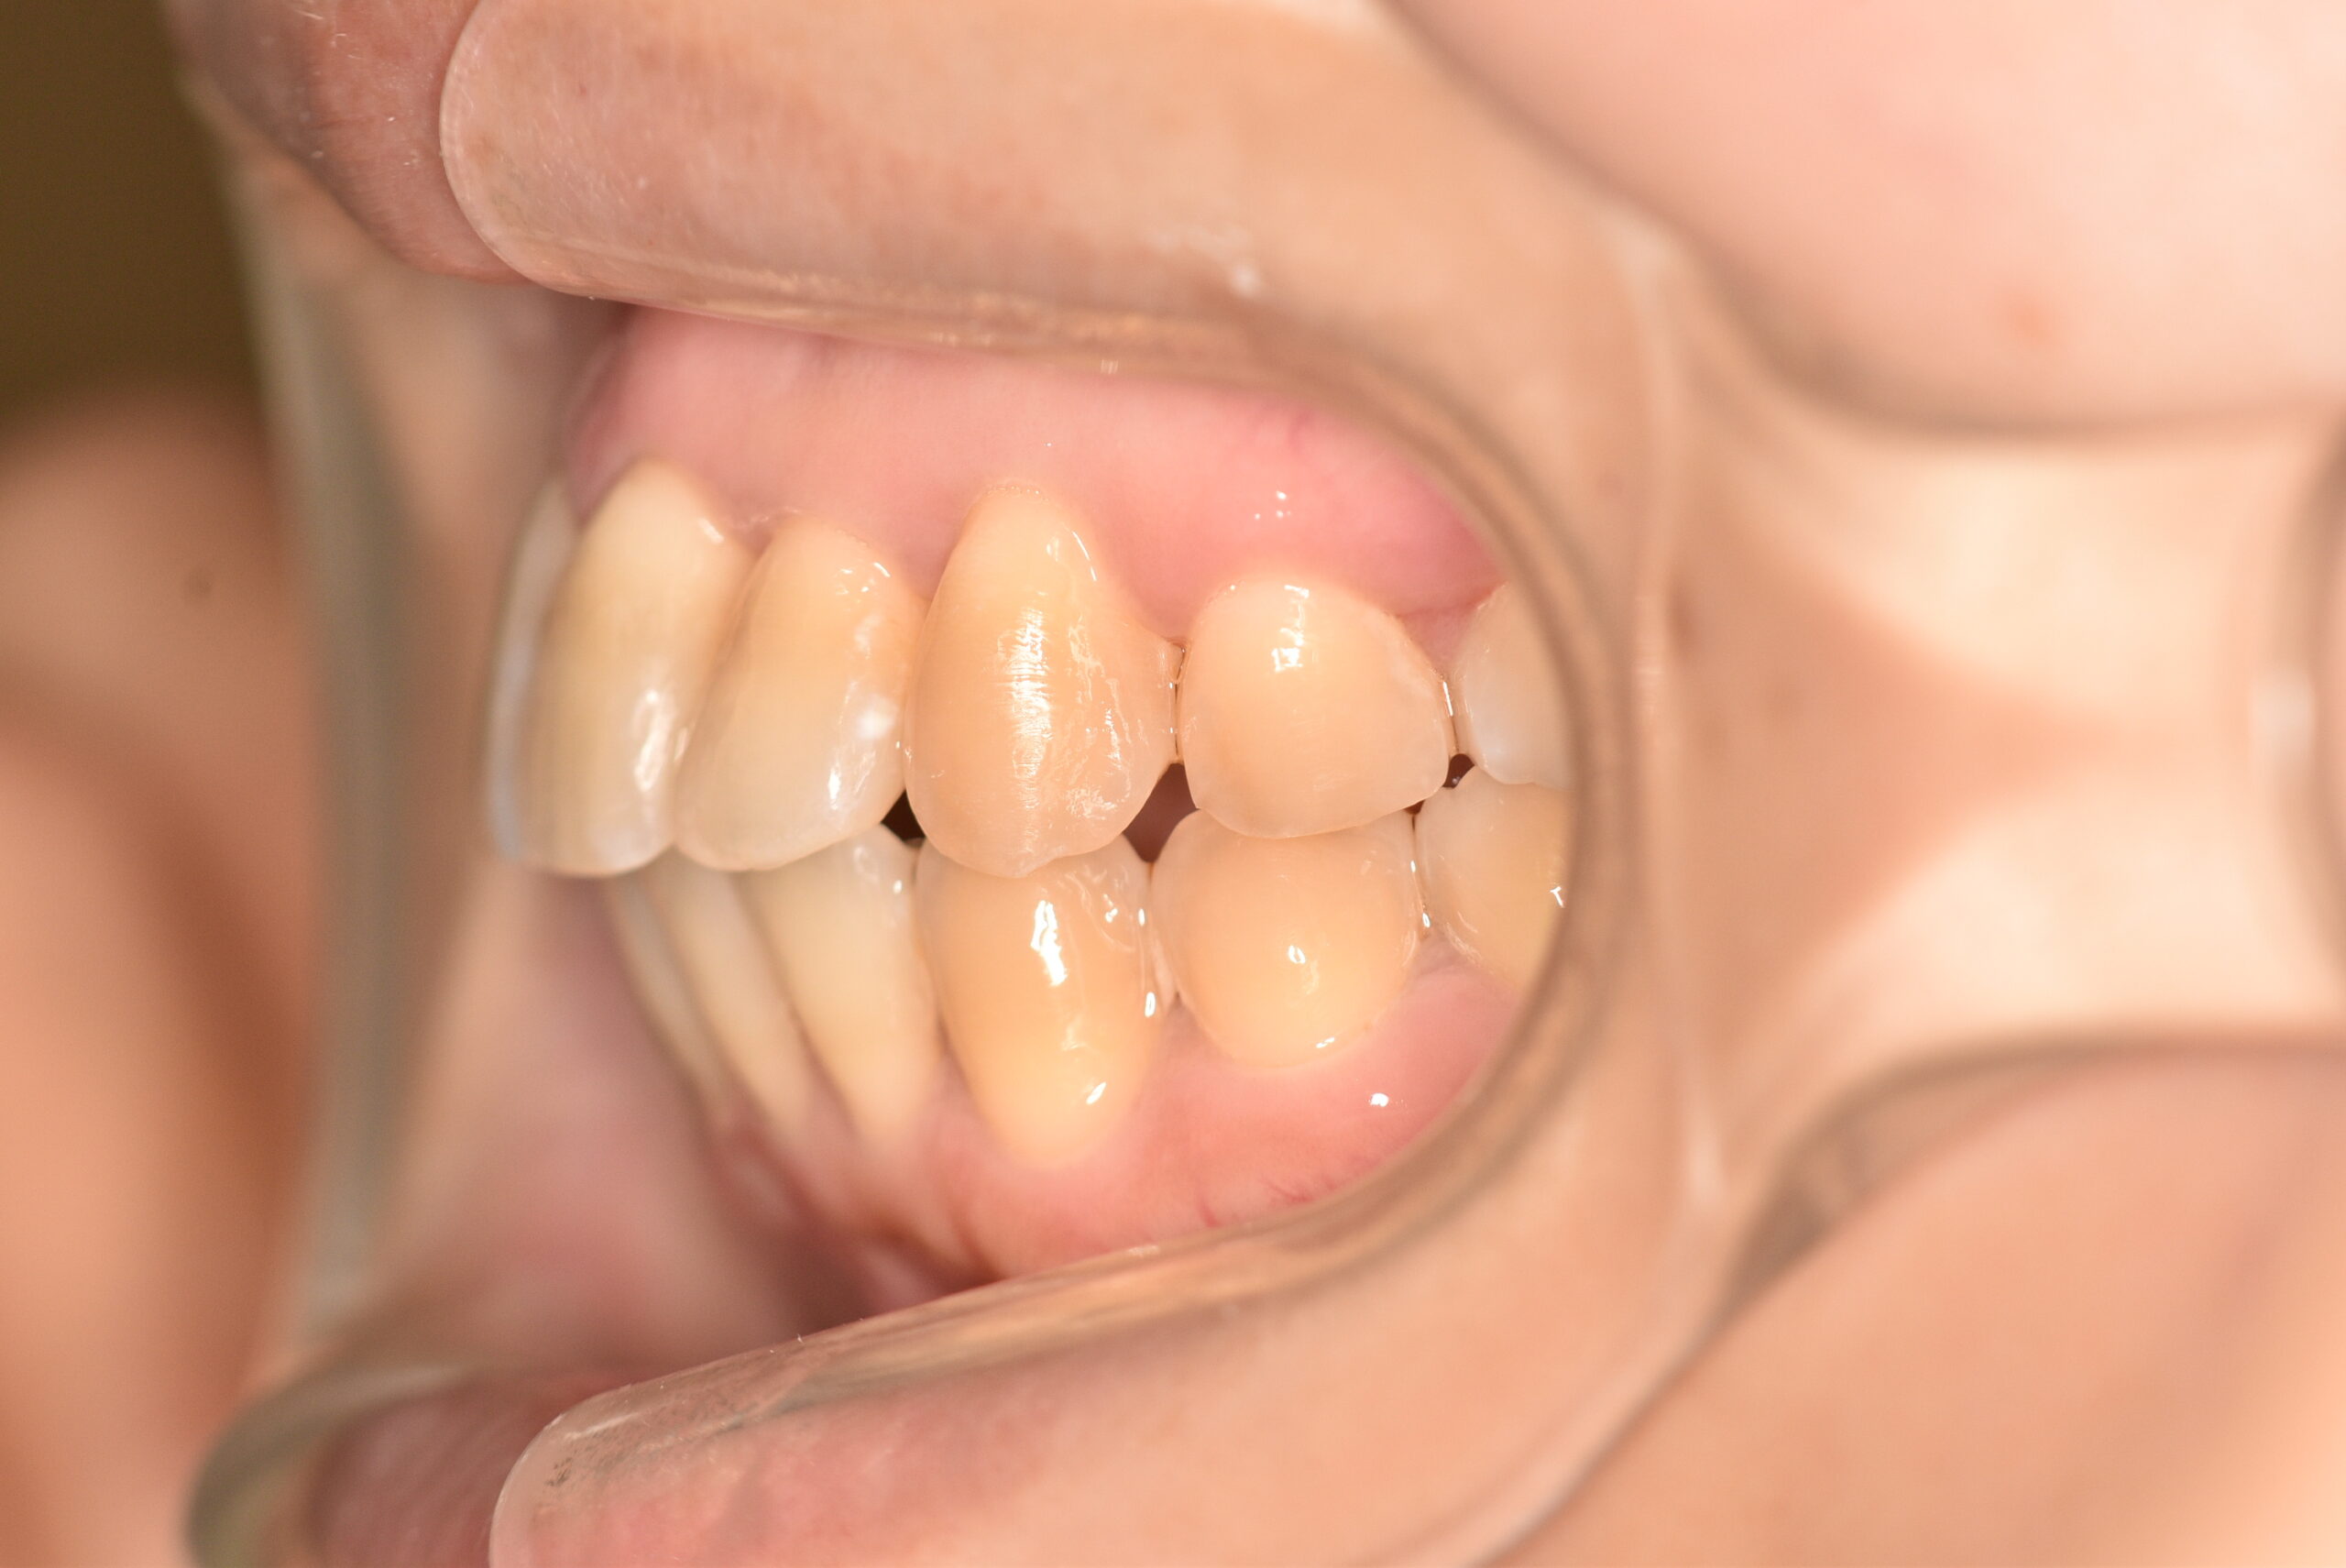

動的治療終了時

症例 症例 症例 症例 症例

治療内容の詳細 初診時31歳の女性で、前歯が奥側にあることを気にされ来院されました。

検査の結果、上下顎叢生を伴うアングルⅠ級不正咬合と診断しました。

治療としては、上顎臼歯部の遠心移動を行い、歯を配列するためのスペースを確保し、非抜歯の上、セルフライゲーションブラケット装置(デーモンシステム)で歯の配列と咬合関係の改善をを行いました。

治療期間は、2年7ヶ月でした。